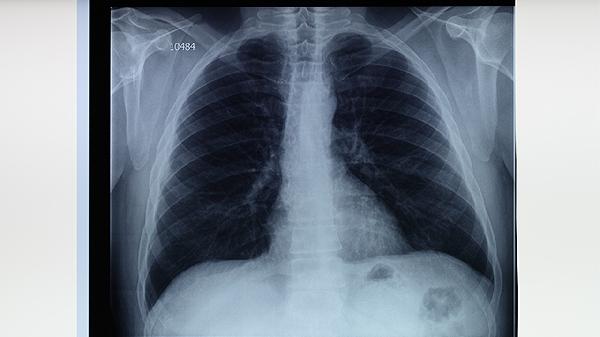

CT扫描对肺结核的诊断具有重要价值,特别在早期病变或复杂病变的识别上表现突出。CT能够检测到普通X光难以发现的微小病灶,帮助医生判断病灶的活动性,例如空洞、结节等典型表现。对于耐药性肺结核或合并其他肺部疾病的患者,CT能提供更细致的影像信息,辅助医生制定治疗方案。

虽然CT诊断准确性高,但仍存在一定局限性。部分肺结核病例的影像表现可能与其他肺部疾病相似,如肺炎、肺癌或真菌感染,导致误诊或漏诊。CT无法直接检测结核分枝杆菌,无法区分活动性和陈旧性病灶,这需要结合痰检或结核菌素试验等实验室检查结果综合判断。